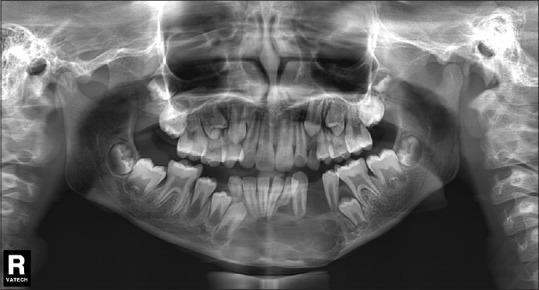

This case series comprises 5 GCG in children between the ages of 4 and 12 years. A retrospective analysis was conducted of all patients who were diagnosed with GCG and treated over 10 years (from August 2004 to August 2014) at Subharti Dental College and Hospital, Meerut, India. The lesions in these children were diagnosed and managed through interdisciplinary collaboration of the Departments of Oral and Maxillofacial Surgery, Oral Pathology and Microbiology and Pediatric Dentistry. Informed consent was obtained from the parents of all the children involved in the study. The analysis was approved by the Institutional Ethical Committee. The demographic details, clinical features, and management approaches of all the patients are listed in Table 1. Detailed history and clinical examination were performed for all the children. An orthopantomogram was taken for all the cases [Figures [Figures11 and and22].

| Figure 2:Preoperative orthopantomogram showing radiolucent central giant cell granuloma of the mandible crossing the midline